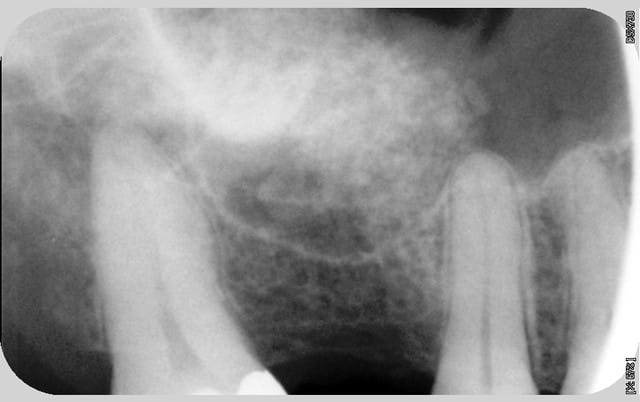

nouvelle radio cette semaine

Tekka n'assume toujours pas.

c'est des krestals? Ça n'a pas l'air dramatique sur la radio. Une petite caractérisation qui me parait logique vu la connexion.

On n'a pas les mêmes critères d'exigences. Perdre 4 mm d'os sur 12 soit 1/3.

Sur 2 ans: 60 krestal posés (au pif) et 10 déposés pour l'instant (certains patients refusent une autre chirurgie)

Attends, sur ces radios t'as 4 mm de perte osseuse? Les vis de cicatrisation sont en place non? Je devine la jonction implant/vis et y a quasiment pas de perte sur tes dernières radio. Enfin je connais pas bien le krestal et la forme de la vis.

Je veux dire, elle est où la perte osseuse sur cette radio? Mais tu as raison, on ne doit pas avoir les même exigences.

La cratérisation est visible beaucoup plus haute: surtout au sondage. L'os que tu vois est en palatin, en vestibulaire, il n'y a plus rien sur cette même longueur.

Sur la molaire, tu ne vois rien aussi.